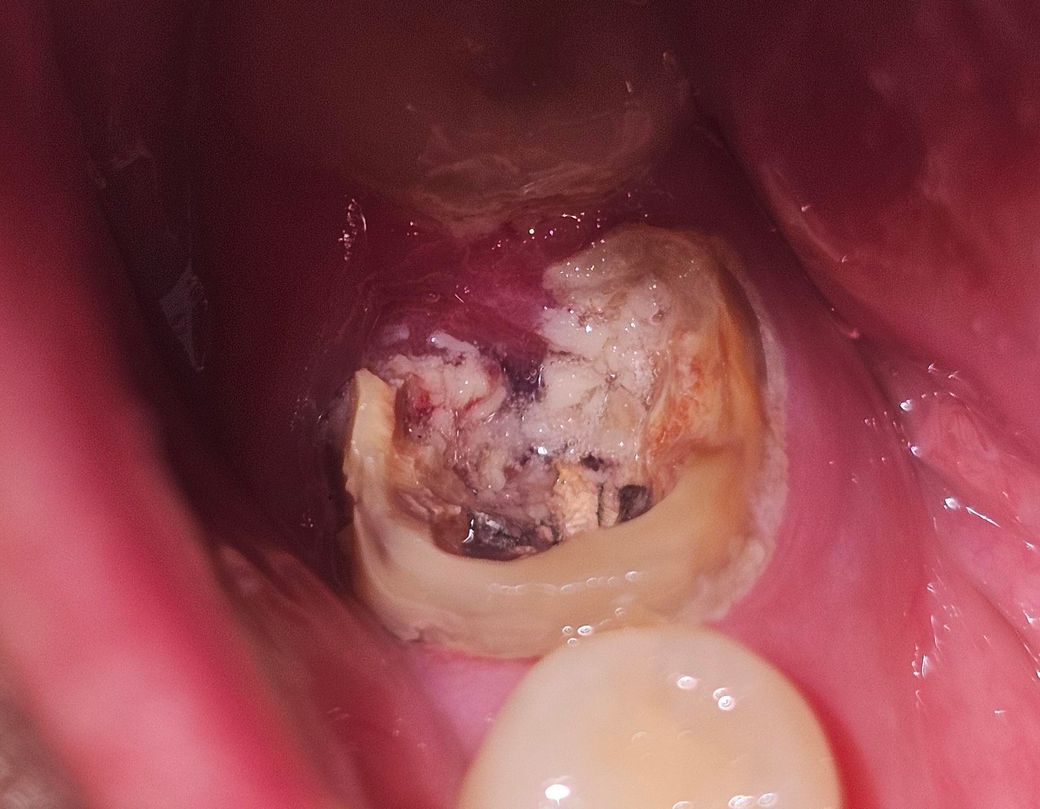

크라운이 썩은 치아와 함깨 빠졌어요 임플란트 해야할까요?

크라운 안쪽이 다 썩은 걸까요?

그냥 크라운이랑 같이 아프지도 않게 쑥 빠졌어요

사진으로 봤을 경우에는 이전에 충치가 깊어서 충치를 치료한 후 크라운 치료를 한 것으로 보입니다. 충치가 치조골 상반까지만 진행되어 있다면 치아를 살려서 쓸 수 있지만 충치가 치죽을 아래로 내려갔다며 치아를 발치해야 할 수 있습니다.

저정도 상태라면 치아를 살리기는 어려울것같고 발치후에임플란트 또는 발치하고 브릿지 치료를 하셔야 될것같습니다.

주조포스트 크라운의 형태로 보이고요 접착제 성분이 휘발되면서 떨어진거 같습니다 좀 깨끗이 정리하고 다듬어서 다시 본뜨고 만드는걸 시도해볼 수 있습니다